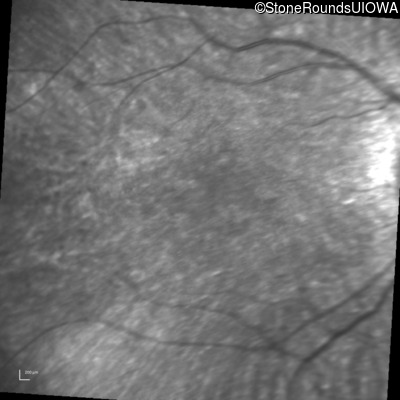

Infrared Fundus Photograph - Left - 20/80

Exemplar